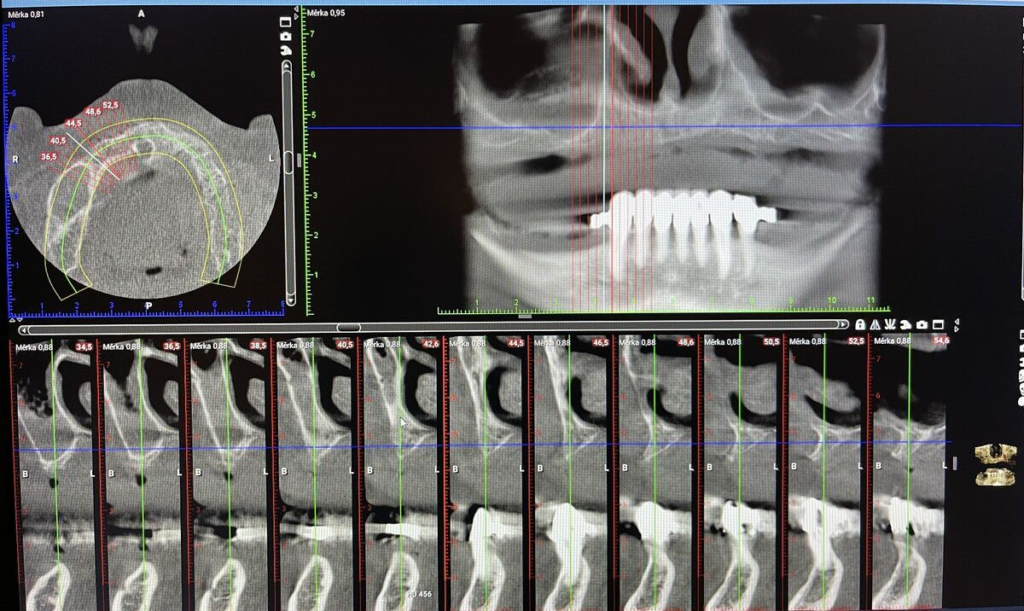

- CBCT 3D snímkování, intraorální skener

- CBCT 3D, vyšetření, fotodokumentace

Technika All-on-X — I. fáze